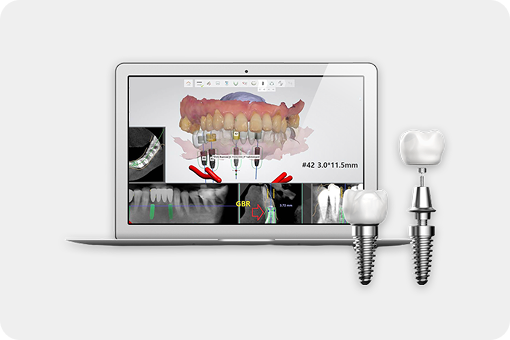

연세준치과는 숙련된 의료진의 경험과 첨단 디지털 장비로

데이터 기반의 과학적인 분석과 예측을 통해

더욱 빠르고 정확한 결과를 제공합니다.